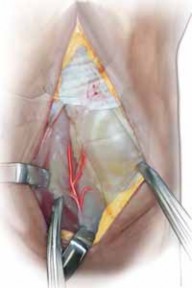

With the lunate prepared, the vascularized bone graft is harvested from the dorsal distal radius. We prefer the 4th/5th ECA pedicled graft. The 5th ECA is identified within the septum between the fourth and fifth extensor compartments. It is traced distally to its anastomosis with the 4th ECA. A bone block, typically measuring 10mm x 5mm x 5mm, is designed over the dorsal metaphysis of the radius, centered on the nutrient branches of the 4th ECA.

Using fine osteotomes, the cortical-cancellous bone block is carefully elevated. The pedicle is mobilized proximally, taking great care to separate it from the underlying posterior interosseous nerve (PIN). A cuff of periosteum and retinacular tissue is left attached to the bone block and pedicle to protect the delicate microscopic vessels. The tourniquet may be temporarily deflated at this stage to confirm pulsatile bleeding from the cancellous surface of the harvested bone block, ensuring graft viability.

Graft Inset and Final Fixation

The vascularized bone block is then gently rotated distally on its pedicle toward the lunate defect. The pedicle must not be twisted, kinked, or placed under any tension. If the lunate defect is larger than the vascularized